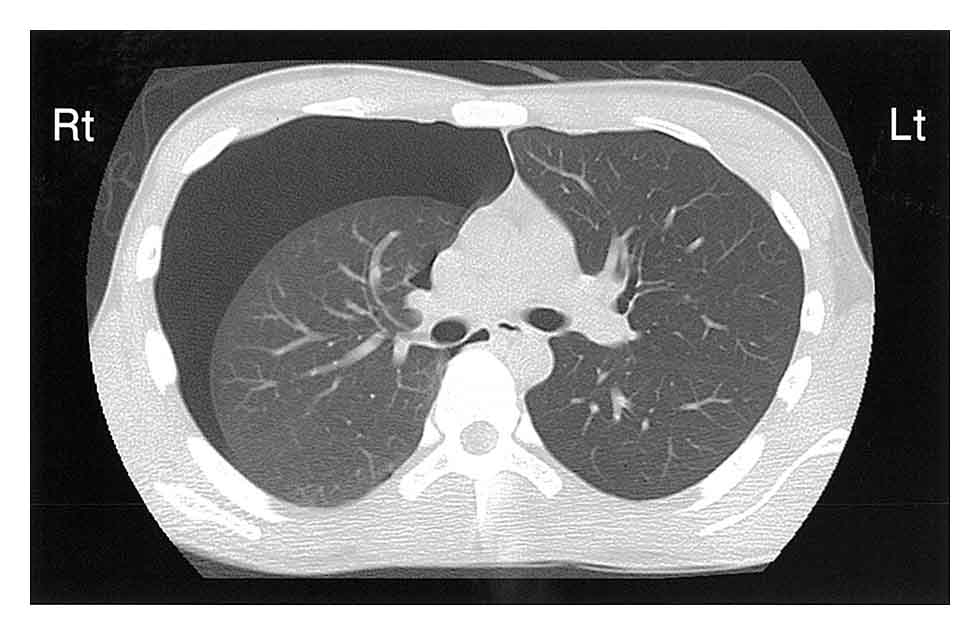

Aさん(27歳、男性)は、突然の胸痛と呼吸困難があり、救急外来を受診した。意識は清明。身長179cm、体重63kg、胸郭は扁平である。20歳から1日50本の喫煙をしている。バイタルサインは、体温36.1℃、呼吸数22/分、経皮的動脈血酸素飽和度(SpO2)96%(room air)である。胸部CT(巻頭視覚素材2)を示す。

Aさんの所見から考えられるのはどれか。

- 3. 右肺野の呼吸音は減弱している。

- 4. 左胸腔内は液体成分で占められている。